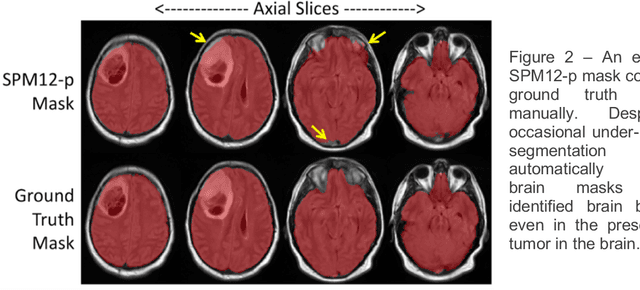

Abstract:Whole brain extraction, also known as skull stripping, is a process in neuroimaging in which non-brain tissue such as skull, eyeballs, skin, etc. are removed from neuroimages. Skull striping is a preliminary step in presurgical planning, cortical reconstruction, and automatic tumor segmentation. Despite a plethora of skull stripping approaches in the literature, few are sufficiently accurate for processing pathology-presenting MRIs, especially MRIs with brain tumors. In this work we propose a deep learning approach for skull striping common MRI sequences in oncology such as T1-weighted with gadolinium contrast (T1Gd) and T2-weighted fluid attenuated inversion recovery (FLAIR) in patients with brain tumors. We automatically created gray matter, white matter, and CSF probability masks using SPM12 software and merged the masks into one for a final whole-brain mask for model training. Dice agreement, sensitivity, and specificity of the model (referred herein as DeepBrain) was tested against manual brain masks. To assess data efficiency, we retrained our models using progressively fewer training data examples and calculated average dice scores on the test set for the models trained in each round. Further, we tested our model against MRI of healthy brains from the LBP40A dataset. Overall, DeepBrain yielded an average dice score of 94.5%, sensitivity of 96.4%, and specificity of 98.5% on brain tumor data. For healthy brains, model performance improved to a dice score of 96.2%, sensitivity of 96.6% and specificity of 99.2%. The data efficiency experiment showed that, for this specific task, comparable levels of accuracy could have been achieved with as few as 50 training samples. In conclusion, this study demonstrated that a deep learning model trained on minimally processed automatically-generated labels can generate more accurate brain masks on MRI of brain tumor patients within seconds.